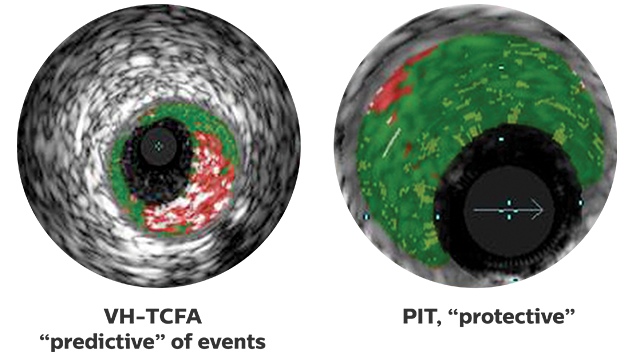

VH IVUS may help assess lesion risk:

Landing stent edges in necrotic core increases the risk of stent thrombosis.3 With VH IVUS, the location of necrotic core can be identified and stent placement optimized.

In acute myocardial infarction patients, the plaque ruptures that cause clinical events are often located proximal to the angiographic narrowing, with geographic miss resulting 60% of the time.4,5 Grayscale IVUS can identify the rupture site, and in addition VH IVUS can show how far the associated necrotic core extends.